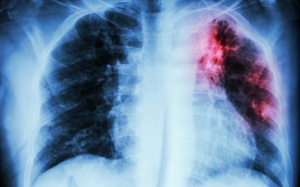

Một phần tư những ca tử vong vì ung thư ở cả nam và nữ trên thế giới là do ung thư phổi gây ra. Bạn càng phát hiện sớm bao nhiêu thì việc điều trị ung thư càng hiệu quả bấy nhiêu. Hãy...